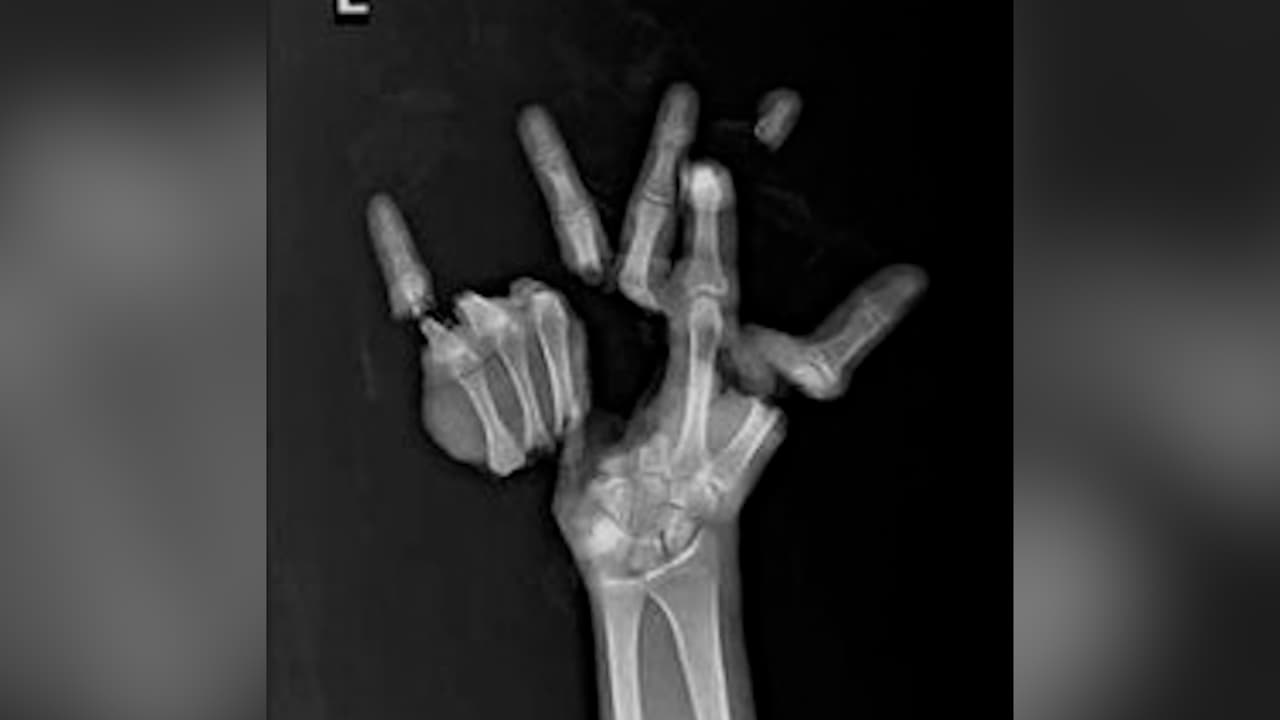

Un niño de 14 años sufrió lesiones significativas en la mano como resultado de la detonación del fuego artificial.

Mientras caminaba por un sendero cercano fuera del campus, el joven encendió el artefacto y este explotó en su mano, causando graves heridas que resultaron en la amputación de gran parte de su mano derecha.